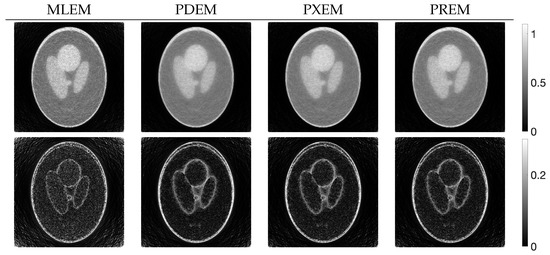

Figure 4 shows the reconstructed images obtained by each iterative method, along with the absolute subtraction images from the true image. Each of the display ranges of the reconstructed images and the subtraction images are unified for the sake of comparison. The reconstruction produced by MLEM was affected by projection noise, whereas those produced by PDEM, PXEM, and PREM showed fewer effects of noise. The quality of the images reconstructed by PXEM and PREM, in terms of preserving edges, will be discussed by referring to results from other phantoms. The high quality of the images reconstructed by PXEM and PREM is also evident from the graphs of MS-SSIM and PSNR shown in Figure 5. Specifically, it is found that PXEM provides a better quantitative evaluation compared with MLEM and PDEM in all iterations and that PREM performs similarly to PXEM.

Figure 4.

Images reconstructed from Shepp–Logan phantom images using MLEM, PDEM, PXEM, and PREM (upper) and their corresponding subtraction images (lower).